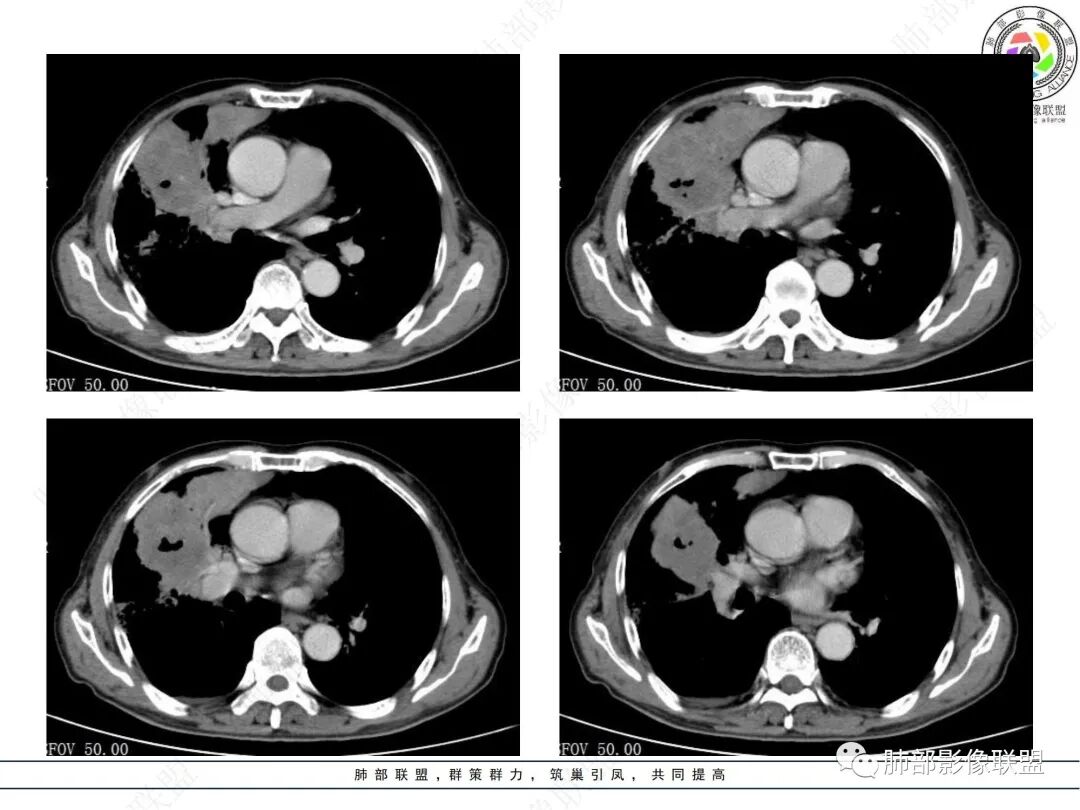

两个病灶独立,又有关联性,内侧病灶近端的支气管包绕在外侧病灶之中,但是走形自然

内部大片坏死区,其中还有不规则空洞

坏死腔内壁清,有强化环

血管征也明显

肺动脉在实变区走形自然,坏死腔周围受压推移,走形自然,坏死区内破坏

周围GGO,不能考虑癌性淋巴管炎

这类坏死区内空洞,提示坏死液比较粘稠

不是液化坏死,液化坏死,这么大,有气体进来按理会形成液气平面

凝固性坏死